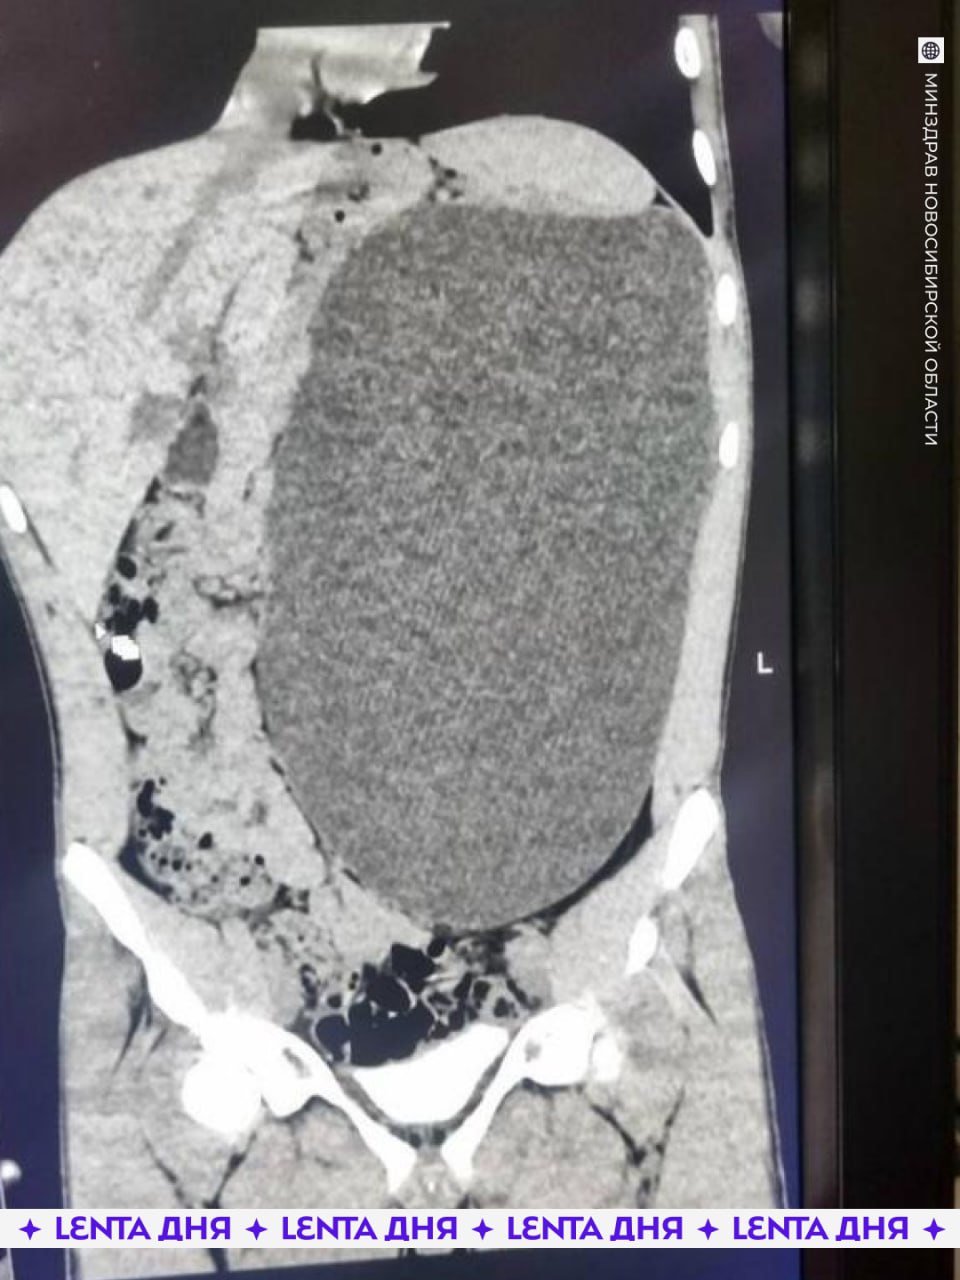

В Новосибирске у подростка удалили почку размером с пятилитровую бутылку Как отметили в больнице это была настоящая бомба замедленного действия случайный удар в живот и мешок мог разорваться До обследования подросток не испытывал никаких симптомов и считал себя полностью здоровым Фото Telegram канал Министерства здравоохранения Новосибирской области

Почка размером с пятилитровую бутылку выросла у подростка Образование заняло почти весь живот и сдавливало внутренние органы При этом 17 летний парень из Новосибирска не чувствовал никаких симптомов и считал себя абсолютно здоровым Любой сильный удар в живот мог закончиться очень плохо Четыре дня врачи откачивали жидкость а затем удалили поражённую почку сейчас подросток идёт на поправку НМШ

У подростка обнаружили почку размером с пятилитровую бутылку Она занимала почти весь живот и сдавливала остальные органы 17 летний новосибирец не испытывал никаких симптомов и считал себя полностью здоровым Врачи нашли патологию случайно и назвали её бомбой замедленного действия случайный удар по животу мог привести к разрыву этого образования В течение четырёх дней хирурги откачивали скопившуюся жидкость а затем удалили поражённую почку Сейчас пациент идёт на поправку хорошо что всё закончилось благополучно Подпишись на Ленту дня в MAX Участвуй в розыгрыше